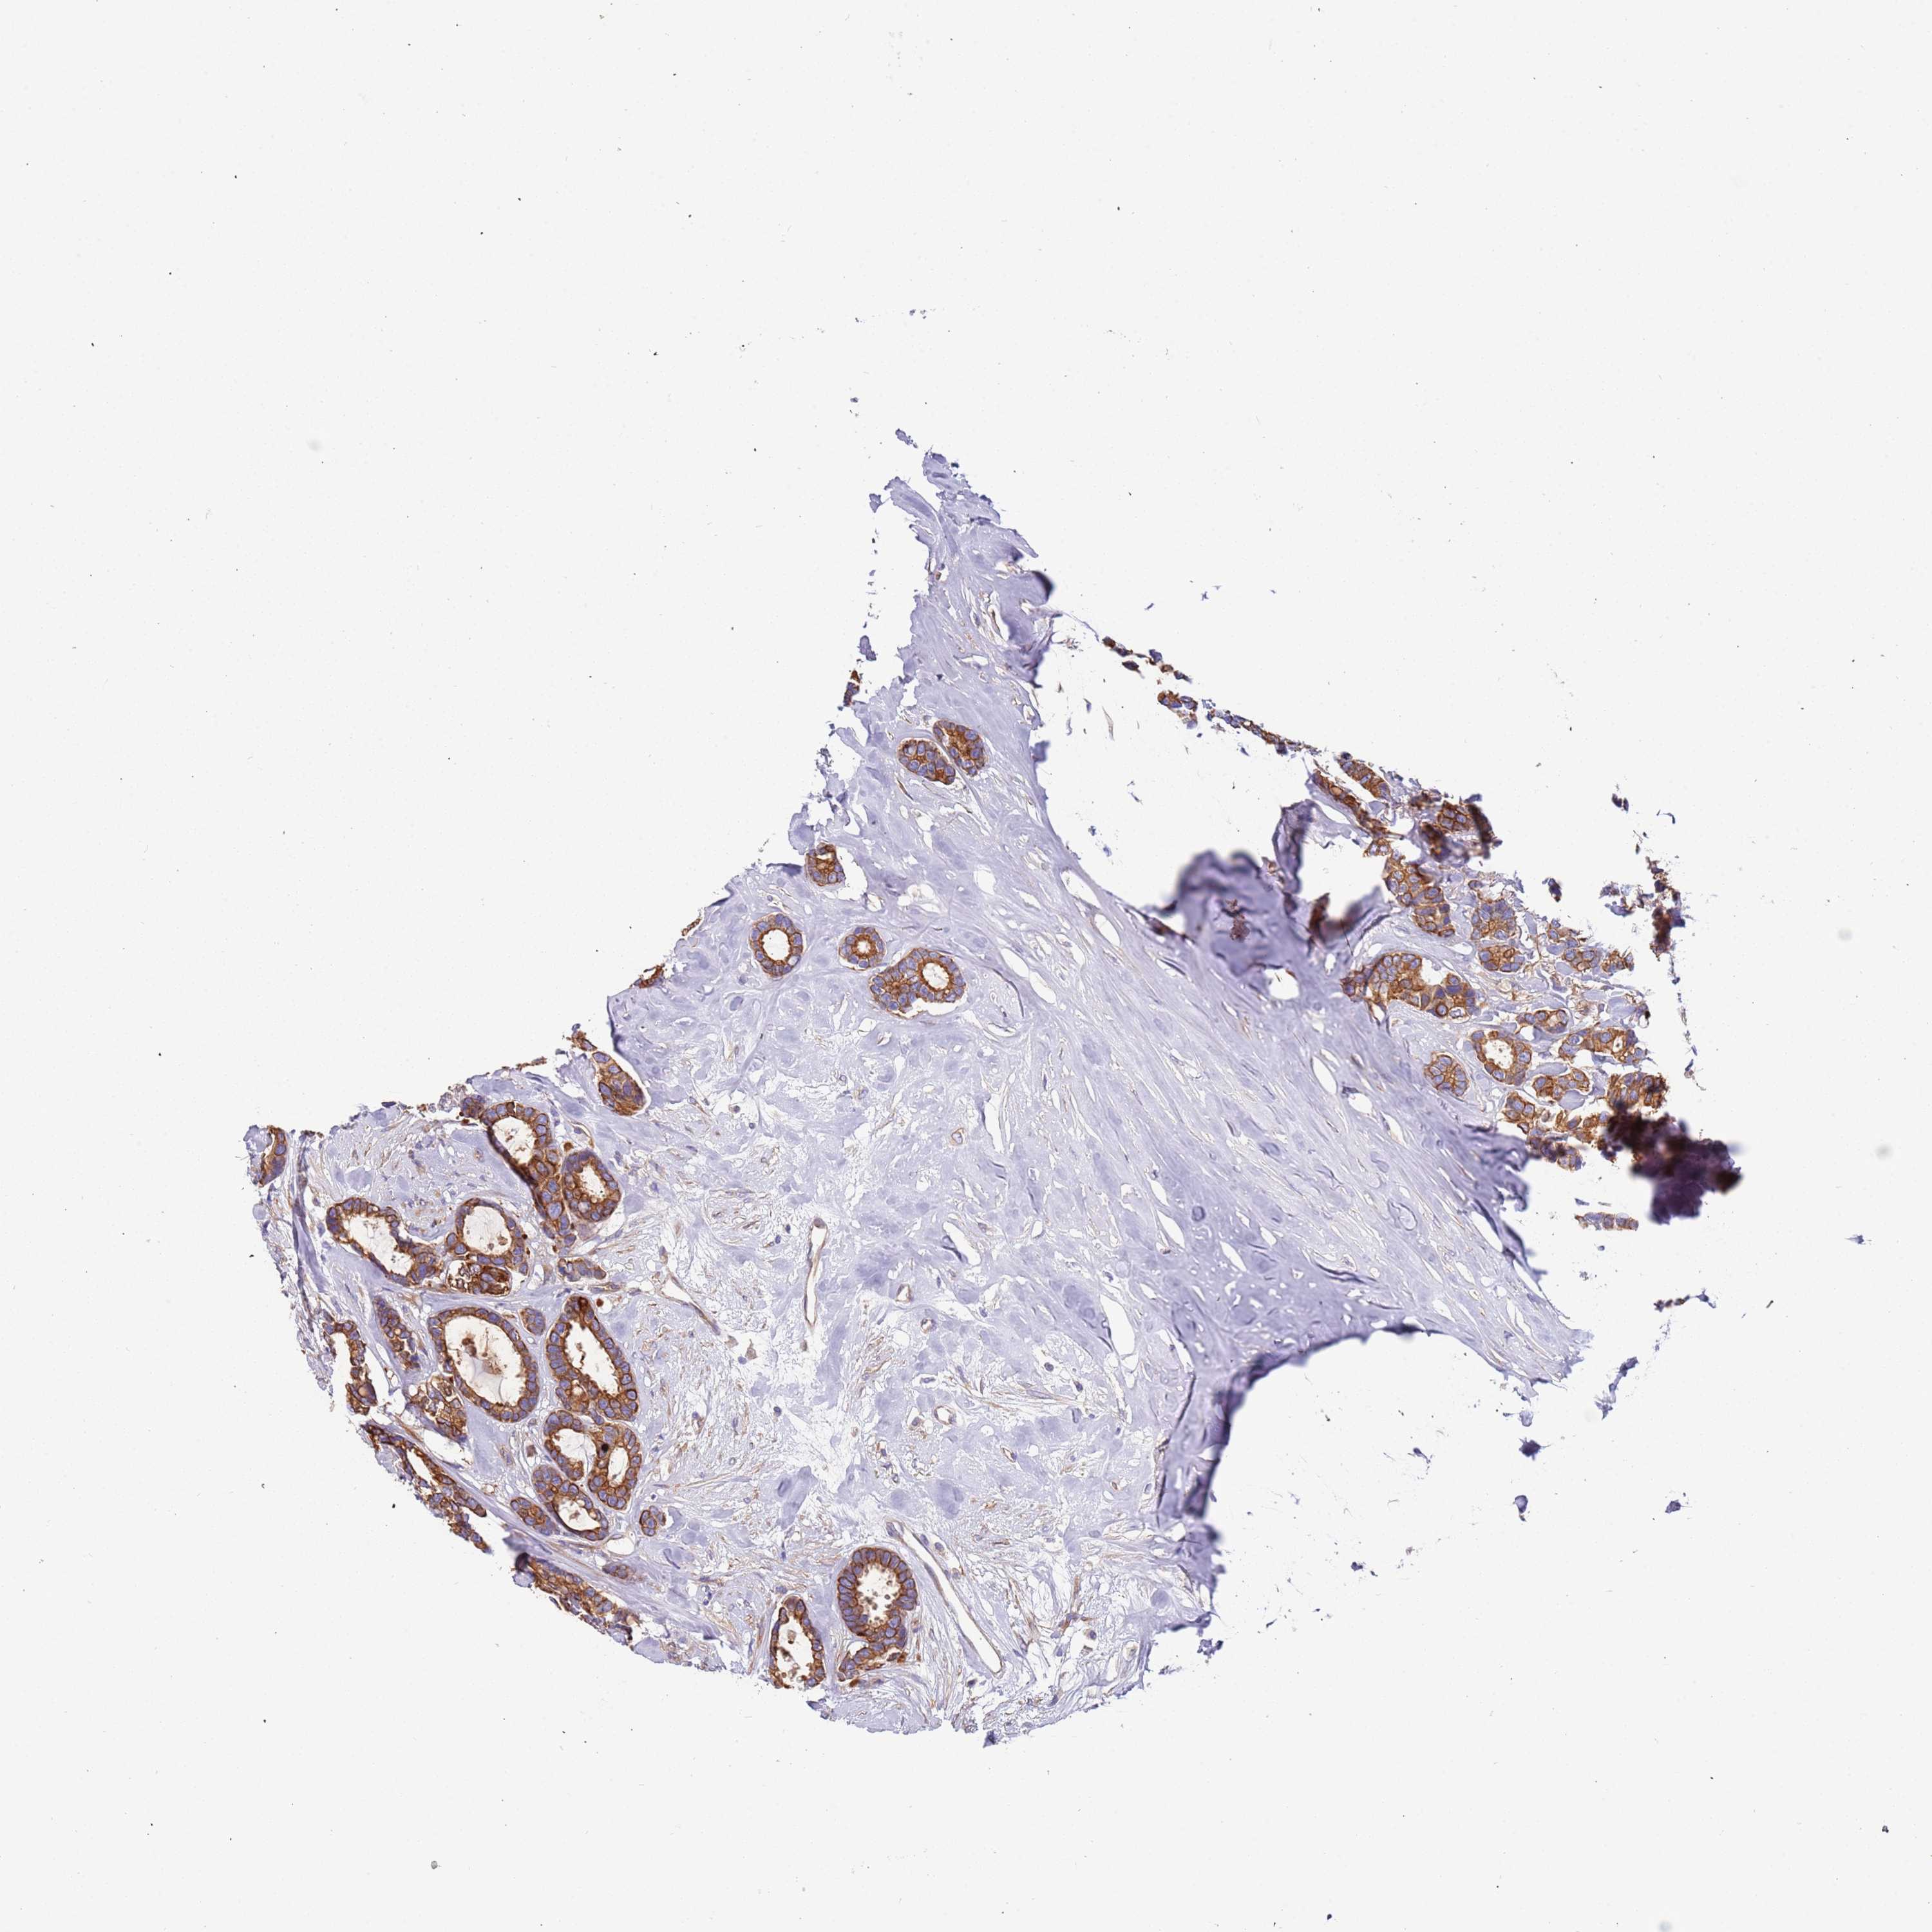

CANCER BREAST CANCER Show tissue menu

BRCA TCGA BRCA VALIDATION PROTEIN EXPRESSION

ANTIBODIES

AND

VALIDATION